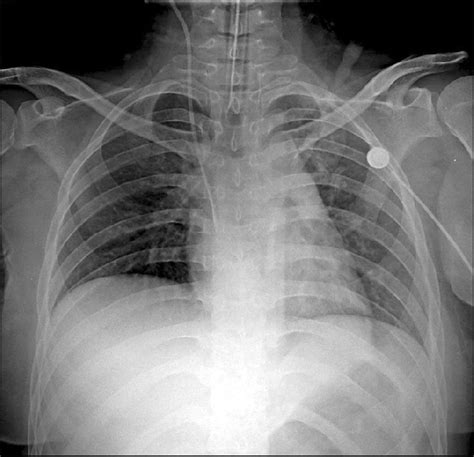

Visualizing the Signs on an X-ray

Alright guys, let’s get into the nitty-gritty of what doctors actually see on a pulmonary interstitial edema x-ray . When we talk about visualizing these signs, we’re essentially looking for indirect evidence of that excess fluid in the lung tissue. As I mentioned, Kerley B lines are a big one. Picture them as really fine, pencil-thin lines, usually a centimeter or two long, running perpendicular to the pleura (the outer lining of the lungs). They’re essentially the thickened walls of the tiny lung lobules due to fluid. They’re often found at the lung bases because fluid tends to settle lower down due to gravity. Another sign is the thickening of the interlobar fissures . These are the fissures that divide the lobes of the lung. Normally, they’re barely visible on an X-ray, but with interstitial edema, the fluid accumulation around them can make them appear more prominent and distinct, almost like sharp, dark lines. You might also notice a generalized increase in bronchovascular markings . These are the lines representing the airways (bronchi) and blood vessels within the lungs. When fluid accumulates in the interstitial space surrounding them, these markings can look more prominent, smudged, or “dirty.” It’s like seeing the trees through a slightly foggy window – the general pattern is there, but it’s less crisp. Sometimes, especially if the edema is more severe or starting to involve the air sacs, you might see what’s called “bat wing” or “butterfly” distribution of haziness or opacities, primarily around the center of the lungs. This pattern is more typical of alveolar edema but can be seen in more advanced interstitial edema too. We also look at the heart size . A significantly enlarged heart on an X-ray is a strong indicator of underlying heart disease, a common cause of pulmonary edema. The pleura itself might show thickening, and you could see blunting of the costophrenic angles if there’s a pleural effusion, which is fluid in the space between the lungs and the chest wall. So, essentially, the radiologist is piecing together these subtle clues – the fine lines, the thickened borders, the hazy patterns, and the heart’s appearance – to build a picture of what’s happening within the lungs. It’s a bit like being a detective, looking for the tell-tale signs of fluid overload that aren’t directly visible but leave their imprint on the X-ray image. The clarity and angle of the X-ray (PA and lateral views are standard) are crucial for spotting these subtle changes effectively. Sometimes, comparison with previous X-rays can be really helpful to see if these changes are new or have progressed.